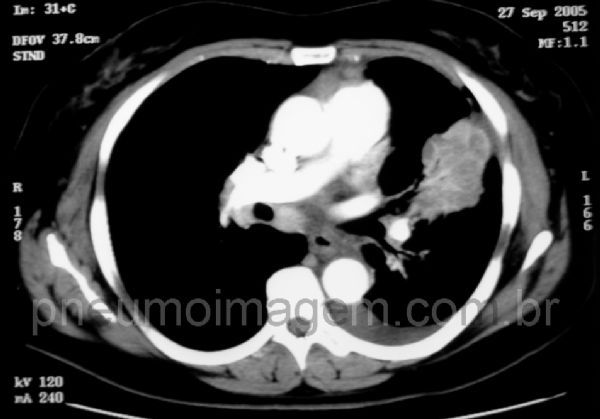

LINFANGITE CARCINOMATOSA

Linfangite carcinomatosa unilateral. O espessamento dos septos interlobulares pode ser liso (setas vermelhas) ou nodular (em rosário) - setas amarelas. Os vasos intralobulares podem estar proeminentes devido ao espessamento intersticial centrolobular (seta azul). Apesar do espessamento septal, não há distorção da arquitetura pulmonar, o que diferencia as alterações da linfagite das alterações da fibrose pulmonar.

Linfangite carcinomatosa pulmonar refere-se ao crescimento tumoral no sistema linfático dos pulmões. É mais comum de ocorrer devido ao câncer de mama, pulmão, estômago, pâncreas, próstata, útero e tireóide. NesSa imagem, observa-se o tumor primário pulmonar.

Carcinomatous lymphangitis refers to tumor growth in the lymphatic system of the lungs. It is more likely to occur due to breast cancer, lung, stomach, pancreas, prostate, uterus and thyroid. In this image, we observe the lung primary tumor.